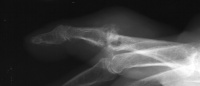

| Right hand tophi involved

the extensor mechanism and a painful unstable index PIP joint. |

| Dorsal tophi diffusely

involved extensor mechanism, joint capsule and MCP joints. |